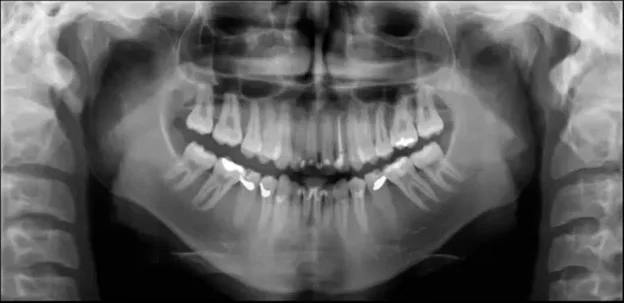

Chin too high or too low

These are also probably a little more obvious for the operator. The first shows the chin positioned too high and therefore, the occlusal plane is at too high of an angle.

Conversely, this patient has the chin too low such that the occlusal is pointing down.

Addressing both of these issues comes down to making sure the occlusal plane is just slightly tipped (~10 degrees) downward. In our experience, we often find that the chin too far up is a more common error. One of the root causes of this is that sometimes the patient is simply nervous. A nervous patient may have a defensive posture that is trying to keep the rest of the body “out of the machine” – which can present as the chin jutting out and up.

To address this issue, there is the obvious technique of raising or lowering the chinrest on your panoramic x-ray and use the laser alignment system to double check this occlusal plane angle. However, another tip is to perform this check last before walking out of the room to initiate the scan.